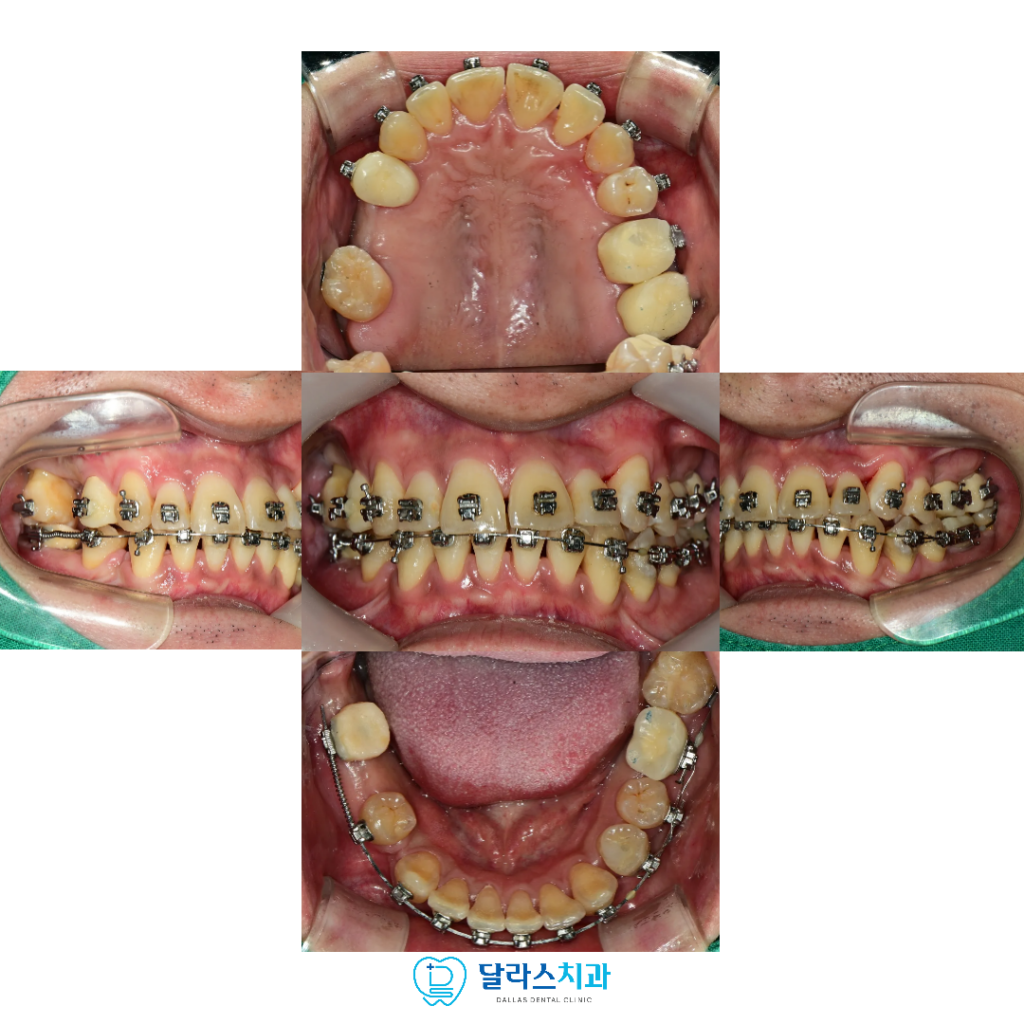

노원치과 치료 과정에서는 어금니의 지지 역할을 회복하는 데 중점을 두어

교합을 안정적으로 만들어 주었고,

턱이 가장 편안한 위치에서 물릴 수 있도록

기준이 되는 교합 위치를 설정한 뒤 치료를 진행하였습니다.

또한 발치 치아를 가능한 줄이기 위해

아래쪽 사랑니를 교정적으로 이동시켜 새로운 교합 관계를 형성하였고

이를 통해 기능적인 균형을 보다 안정적으로 완성할 수 있었습니다.

교정과 임플란트를 각각 따로 접근하는 것이 아니라

전체적인 치료 흐름 속에서 함께 계획하고 관리함으로써

총 치료기간은 약 2년으로,

치료에 대한 부담을 낮추고 예측 가능한 결과를 만들어 드리고자 하였습니다.